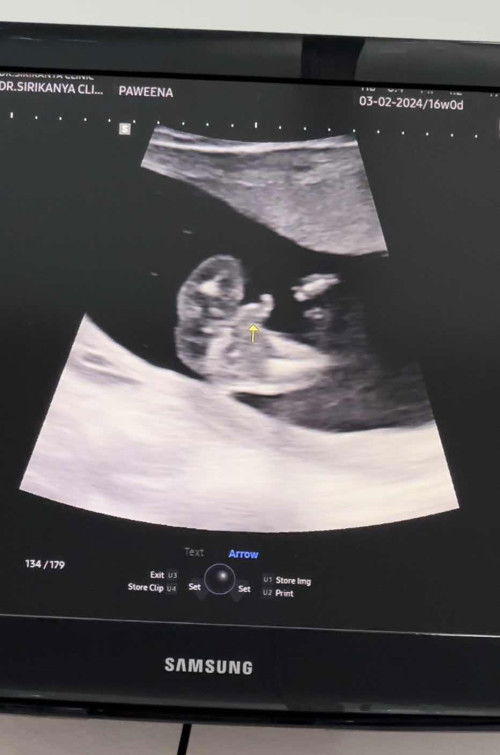

เพศชายไหมค่ะเเบบนี้?

แม่ๆช่วยดูทีค่ะว่า เพศ อะไร #ท้องเเรกจ้า